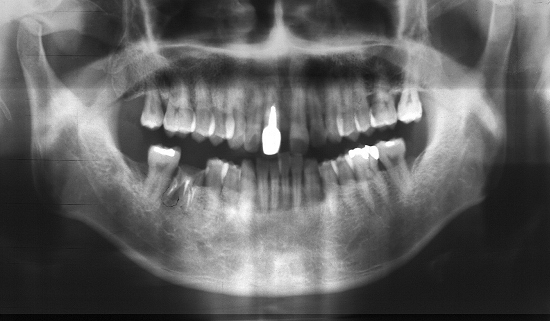

Horizontally Impacted third molar.

Fig.

1 at the age of 16. |

2 at the age of 23. |

3 at the age of 27. |